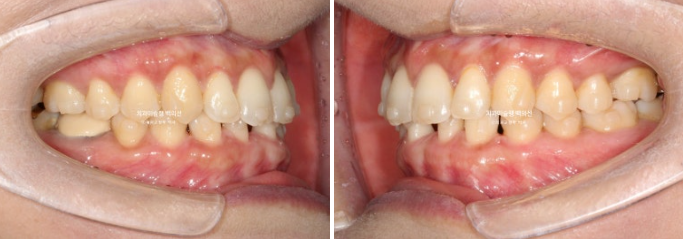

원래 벌어져 있던 공간은 대부분 없어졌으나 미세공간이 아직 남아있습니다.

아래 정가운데 앞니 이외에 다른공간은 모두 닫혔습니다.

쓰러져 있던 두번째 큰어금니는 잘 세웠습니다.